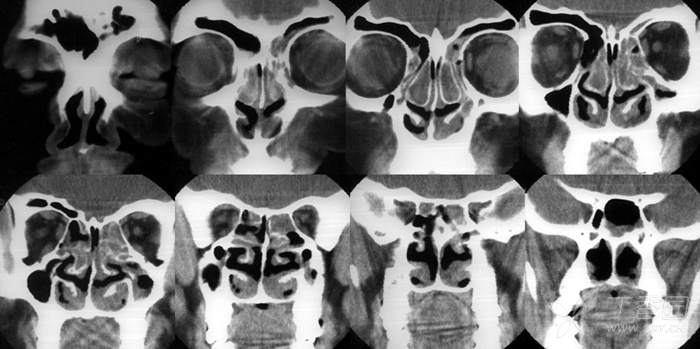

病例2:2004年2月12日手术,从手术创面的广泛性,到术后随访的频繁性,同样非常严重,站在今天鼻-鼻窦剔骨法成形术的角度,对于这样的做法和结果,既无法理解,更难以接受(见下图及图中的时间标示)。